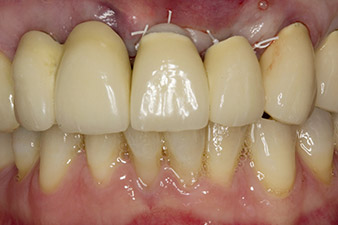

Bei der Erstvorstellung sind die Zähne 21, 22 und 23 mit 19 Jahre alten verblockten Kronen versorgt. Sie sind über ein Geschiebe mit Implantaten an den Positionen 12/11 verbunden (vgl. Abb. 2). Das Röntgenbild zeigt einen horizontalen Knochenverlust um die Zähne 21 und 22 (Abb. 1).

Nach primärer Abheilung werden die Weichgewebe mithilfe der basal unterfütterten Brücke ausgeformt. Zwei Monate später erfolgt die Freilegung mit einem leicht palatinal gelegten Kieferkammschnitt (Abb. 2).